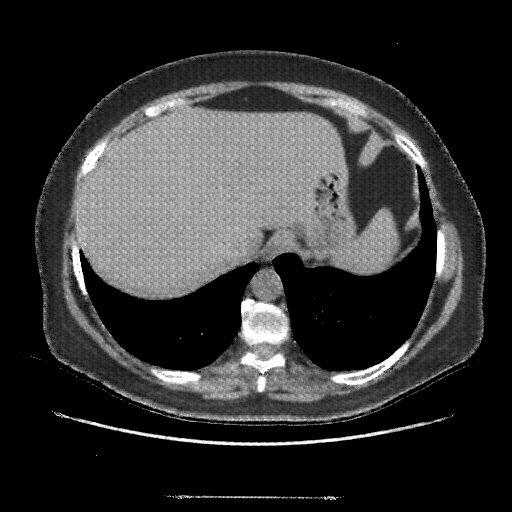

Image Grid

4Γ—3 grid: Rows show different image types (Original NATIVE, Reconstructed NATIVE, Original VENOUS, Generated VENOUS), Columns show windowing techniques (No Window, Lung Window, Mediastinum Window)

Reconstructed NATIVE CT scan (cycle consistency)

Full window (WL 1023.5, WW 4095 β†’ Low βˆ’1024, High +3071)